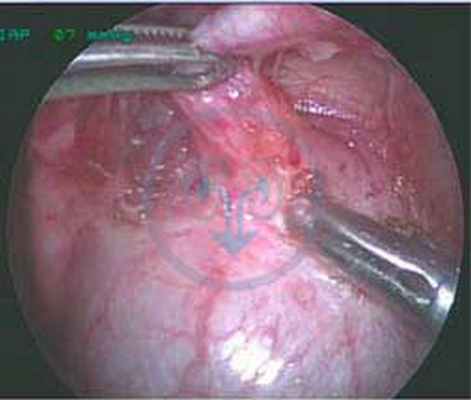

Лечение только хирургическое и заключается в полном иссечении протока от пупка до дна мочевого пузыря. Операция может быть выполнена как лапароскопическим способом, так и с использованием лапаротомного доступа.

![]()

Мочевой проток на эндоскопии

В зависимости от оперативного доступа пациенты находятся в стационаре от 2 до 5-7 дней. В послеоперационном периоде проводится антибактериальная, симптоматическая терапия, ежедневные перевязки.